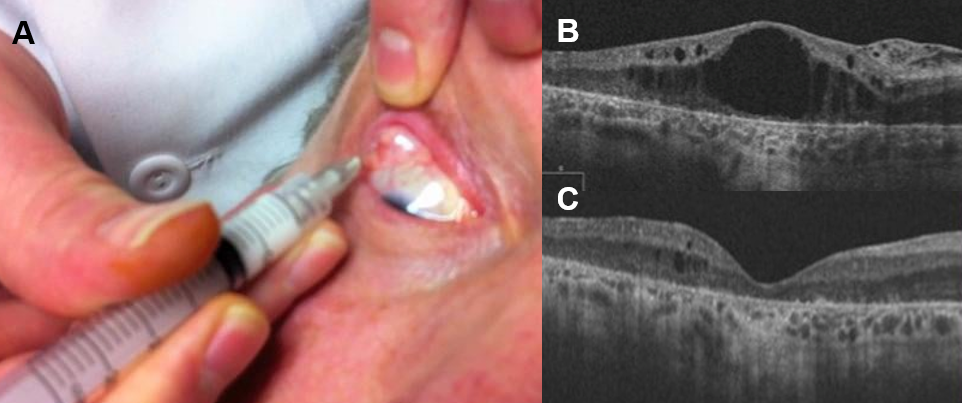

그림 1. (A)테논난하트리암시놀론(Sub-Tenon Triamcinolone) 주입술, (B) 주사 전 CME, (C) 주사 2개월 후 호전-중심 오목 형태가 유지 중 ④ 유리체강 내 주사 ⑤ 트리암시놀론(Triamcinolone, 그림 2-A) : 혈액망막 장벽(Blood Retinal Barrier; BRB) 파괴를 감소시킵니다.* 재발성 CME에 유용하지만 효과가 일시적이기 때문에 일정 기간이 지나면 재발합니다. →효과를 유지하기 위해서는 여러 번 주사를 맞아야 합니다.㉡ 덱사메타손 삽입물(Dextamethasoneimplant; Ozurdex®, 그림2-B&C): 보다 효과가 오래 유지되지만 여전히 재발로부터 자유롭지 못합니다.

그림2.(A) 유리체강내 트리엄시놀론주입, (B)덱사메타손삽입술장면, (C)삽입된 덱사메타손인플랜트(오더덱스)의 유리체강내 모습

그림 3.(A) 주사 전 CME, (B) 덱사메타손 플랜트 삽입술 후 6개월 – 호전된 CME ᅥᆫ시 投与 전신 투여 – 먹는 약 또는 정맥 주사 : 부작용 위험이 크므로 주의하십시오.